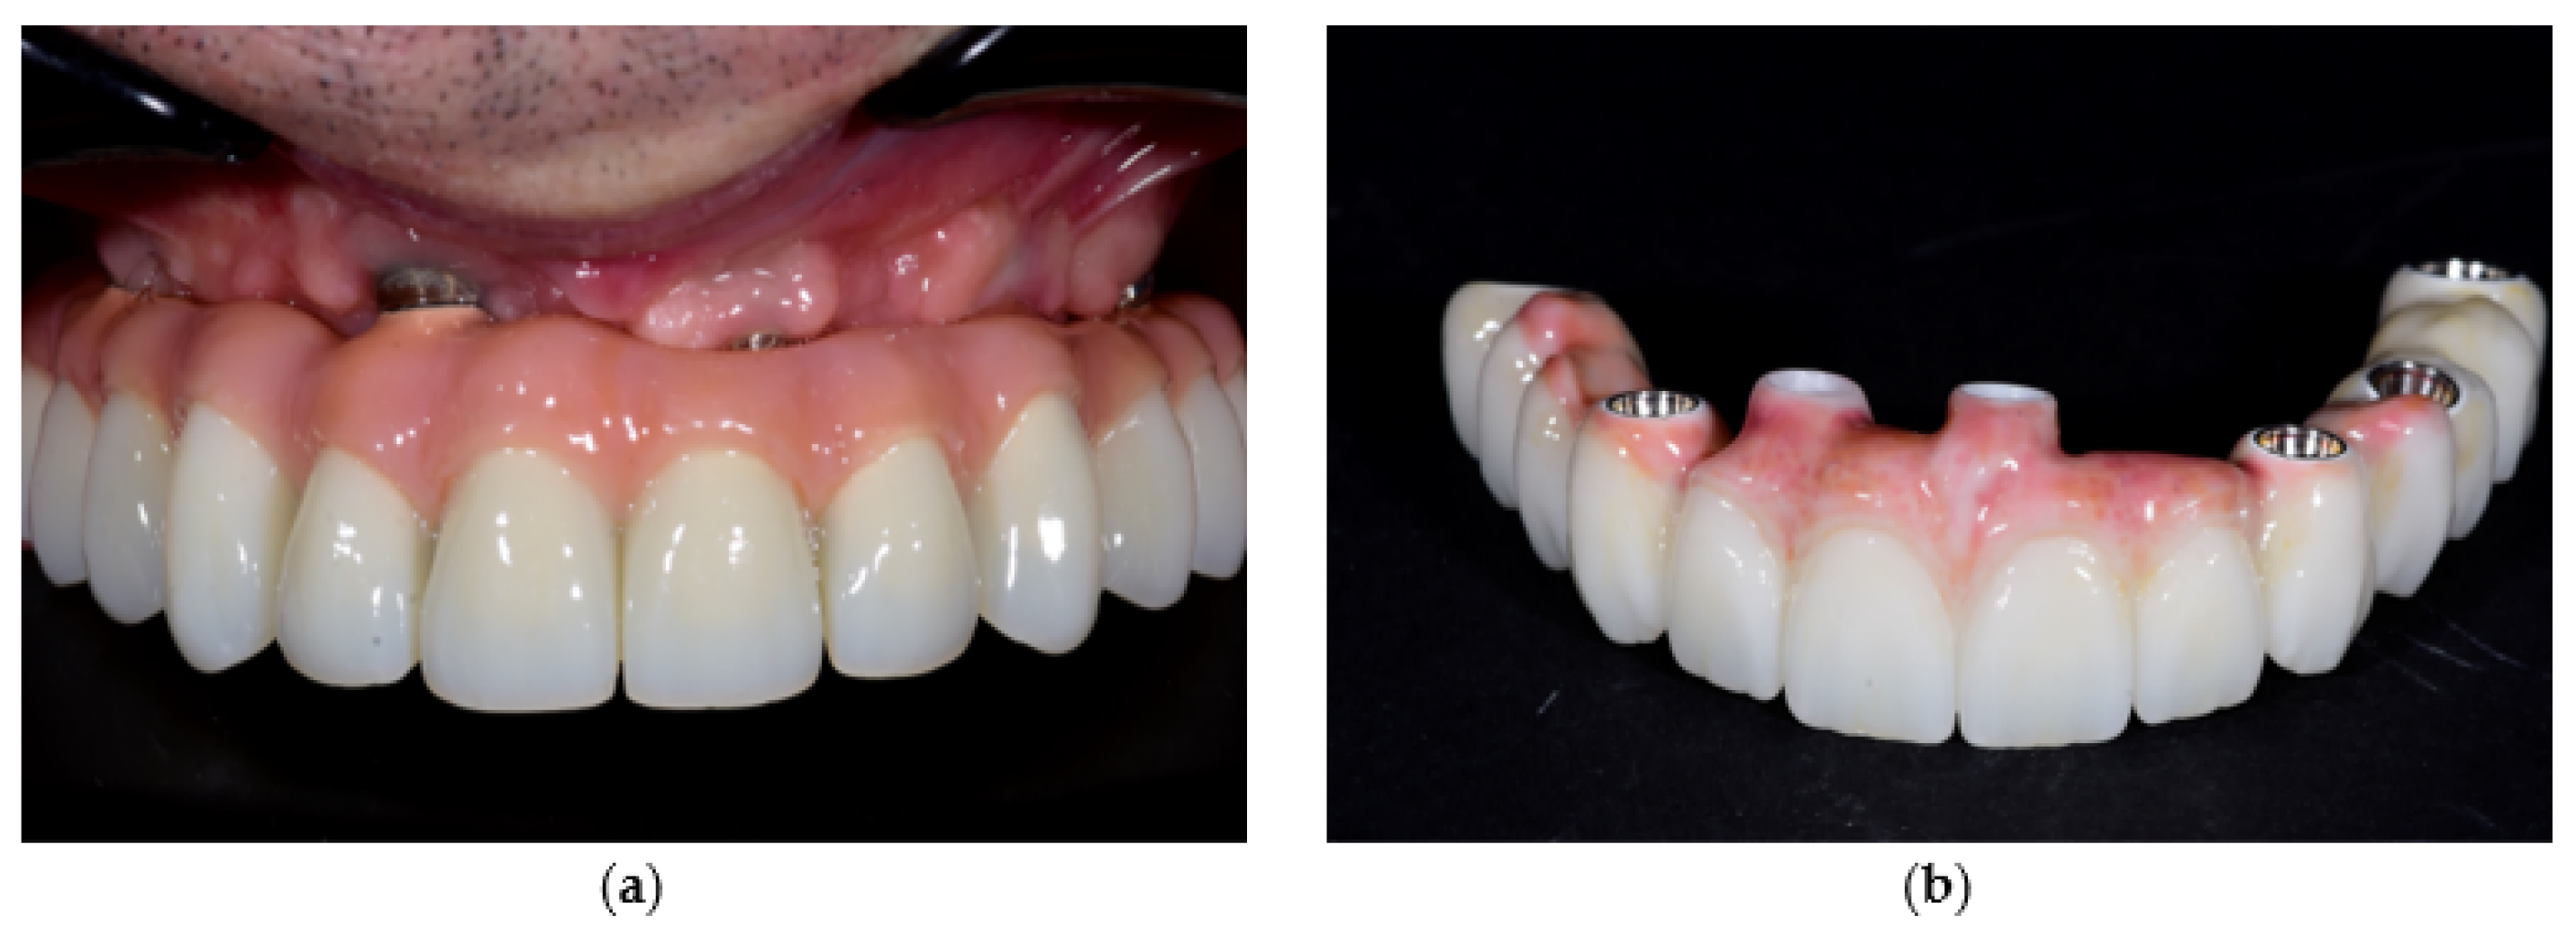

- Prosthetic gingiva adaptation—presence of soft tissue mismatch or loss of adaptation between the prosthetic gingiva and peri-implant soft tissues, documented through standardized frontal and lateral photographs.